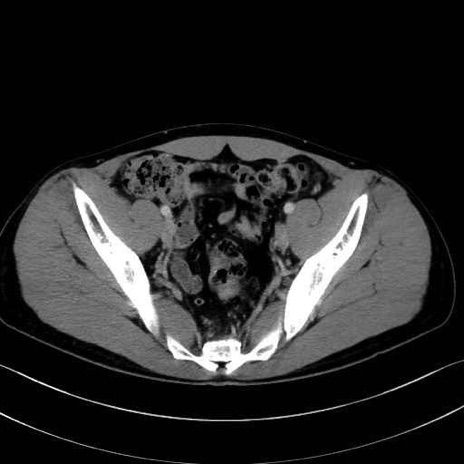

2. 腸腰筋群と骨盤底筋

大腰筋 (Psoas major)

腸骨筋 (Iliacus)

肛門挙筋 (Levator ani)